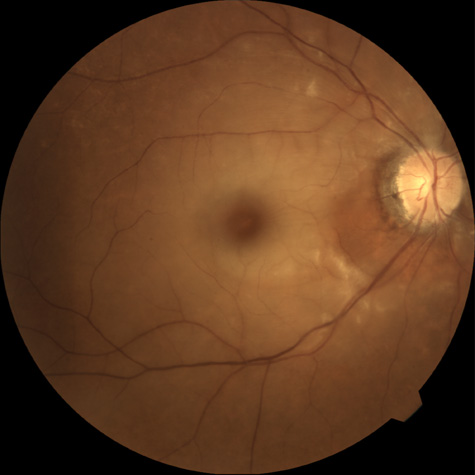

OBSTRUCTION OF A RETINAL ARTERIOLE

Obstruction of a retinal arteriole produces cotton-wool spots, which have also been called white patches or soft exudates (Fig. 7). Cotton-wool spots are caused by focal hypoxia, which obstructs axoplasmic flow, resulting in accumulations of axoplasmic debris in the nerve fiber layers of the retina.142–144 Cotton-wool spots may be either single or multiple. On intravenous fluorescein angiography, they correspond to areas of capillary nonperfusion.6 The patients are often asymptomatic but may experience severe visual loss if the areas of arteriolar obstructions are extensive (Fig. 8).145

Fig. 8. A: Extensive cotton-wool spots and (B) corresponding large areas of vascular nonperfusion in a patient with Purtscher's-like retinopathy associated with systemic lupus erythematosus. The condition was bilateral.

There are multiple causes for cotton-wool spots. Brown and co-workers146 studied 24 consecutive patients who presented with a cotton-wool spot; any patient with known diabetes mellitus was excluded. In this series, 23 of the 24 patients were found to have one or more associated systemic diseases. The disease entities associated with cotton-wool spots are listed in Table 2.

The most common cause of cotton-wool spots is diabetes mellitus, and most of these patients are already aware of their disease. The second most likely cause is either acquired immunodeficiency syndrome or systemic arterial hypertension. Occasionally, a healthy patient has a cotton-wool spot and on systemic evaluation is found to be entirely normal. This was the case with one of Brown and co-workers146 patients, and we have encountered similar patients. However, we have also seen an occasional patient with no history of systemic disease who presented with a single cotton wool spot and subsequently was diagnosed with diabetes.